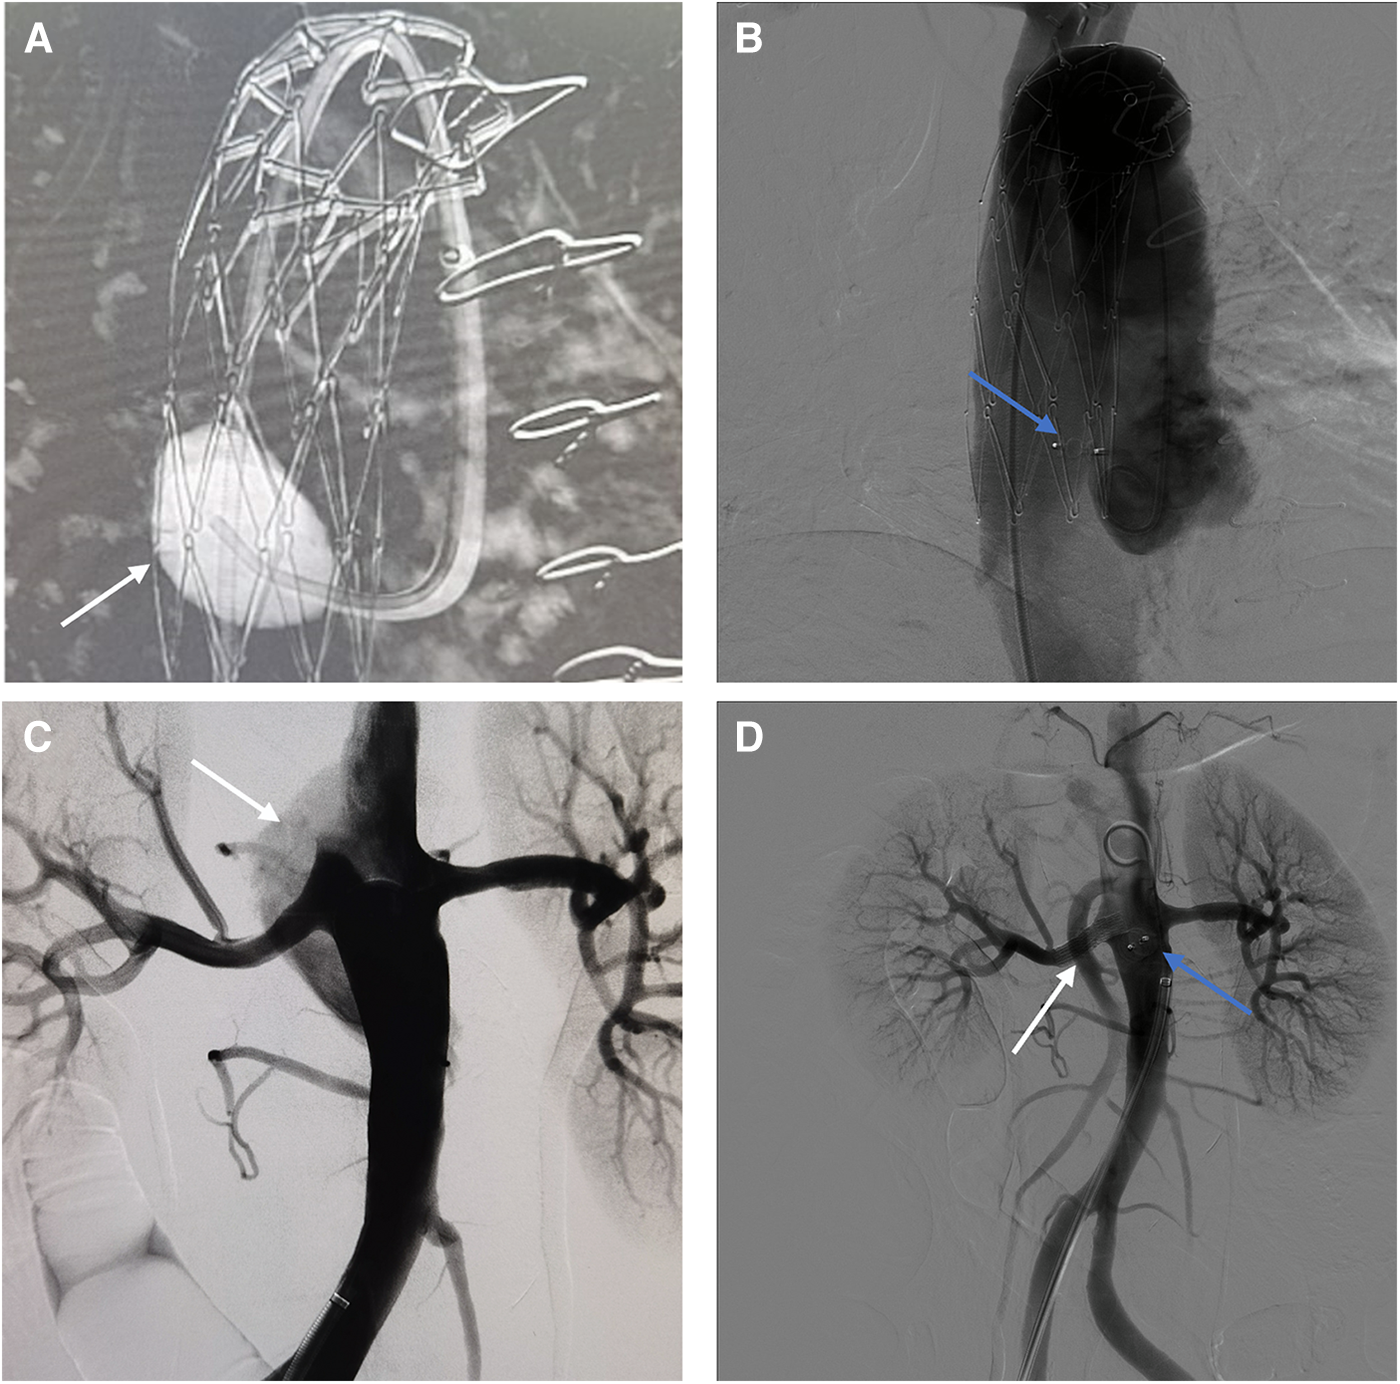

Under general anesthesia, a 6 F catheter was inserted through the right femoral artery to perform false lumen angiography in the ascending aorta (Figure 2A). A 4 mm × 7 mm AVP II was placed in the tear, with two parts in the false lumen and one in the true lumen. Aortography confirmed proper placement of AVP and absence of false lumen opacification (Figure 2B). Abdominal aortography used to find tear near renal artery (Figure 2C). A 7 × 25 mm Viabahn stent (W. L. Gore & Associates, Flagstaff, AZ, USA) was placed in the right renal artery to block the tear at the opening of the renal artery. Then, using a 7F guide catheter, we inserted an AVP II measuring 10 × 7 mm into the tear in the abdominal aorta. Aortography confirmed proper AVP placement with smooth blood flow in the right renal artery stent, and no false lumen opacification (Figure 2D). After 6 months, the follow-up CTA showed complete thrombosis in the false lumen of both the ascending and abdominal aorta without endoleaks. The AVP position remained stable. The abdominal aorta diameter decreased from 51 to 38 mm, while the true lumen diameter increased from 20 to 27 mm (Supplementary Figures S1B,D).

Figure 2

(A) Intraoperative imaging of aneurysm cavity. (white arrow) (B) Use AVP to embolize the tear of ascending aortic. (blue arrow) (C) The false lumen of the abdominal aorta. (white arrow) (D) Final intraoperative angiography showed the AVP (blue arrow) and the stent (white arrow).